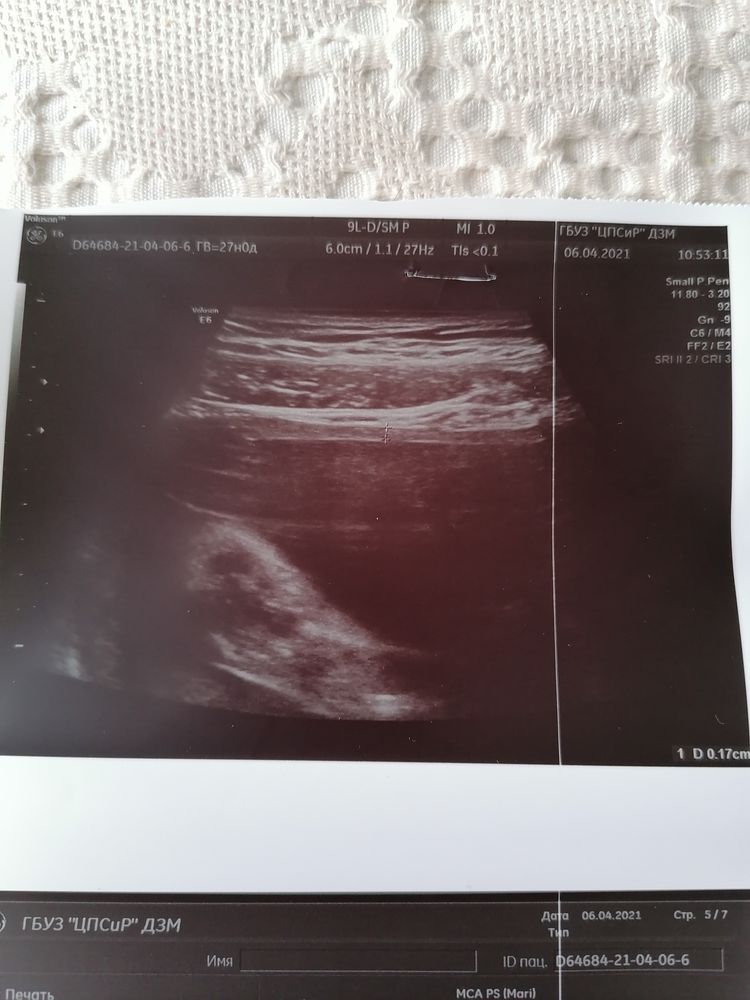

Рубец 1.7мм на сроке 27 недель

Сегодня ездила на узи и обнаружили рубец 1.7мм. Ещё 3 недели назад был 3 мм. Меня это пугает капец как. Ничего не болит, не жгёт. Врач сказала, что он состоятельный. Но блин почему так уменьшился????. Предположили, что из-за того, что сынок лежит в поперечном предлежании и растягивает матку и тем самым тянет рубец.

Мне сегодня смотрели 2 врача и разными датчиками и там и там шов одинаковый 1.7. Прошло уже 4 года от КС.